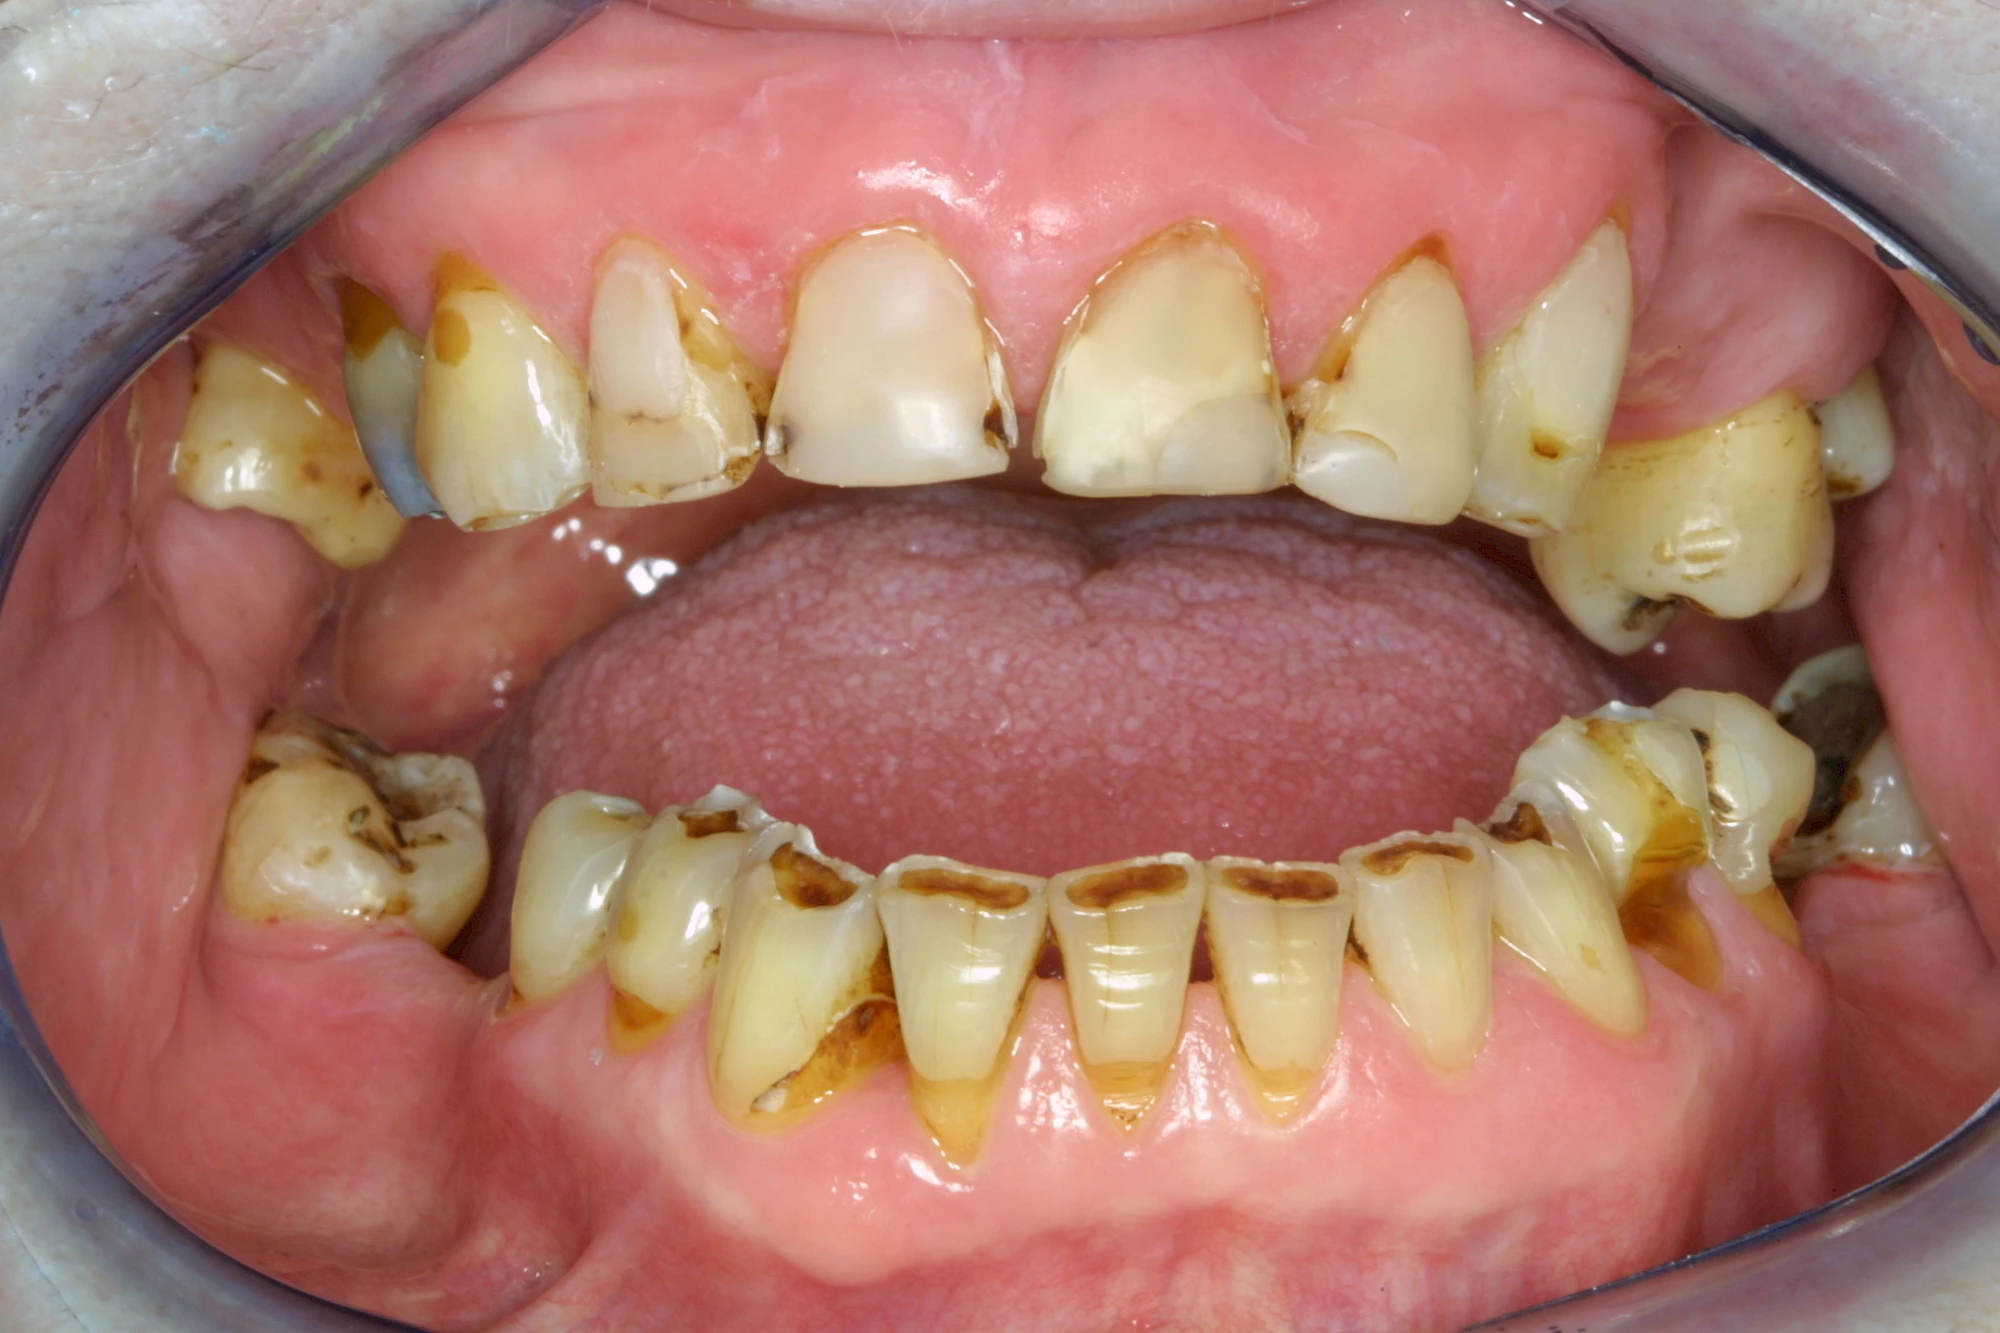

Über die Zeit können verschiedene Prozesse die Zahnhartsubstanzen aufzehren:

- Abnutzung durch Kauen (Abrasion) oder duch durch übermäßiges Knirschen bzw. Pressen (Attrition)

- Säurebedingte Auswaschung (Erosion)

- Knirschen bzw. Pressen und ungünstige Putztechnik (Druck): keilförmige Defekte

Die Zähne können dabei auf Reize (warm, kalt, süß, sauer) oder auch beim Zähneputzen empfindlich oder schmerzhaft sein. In allen diesen Fällen ist es sinnvoll, den Zahnarzt zu kontaktieren und das weitere Vorgehen abzustimmen.

Auswaschung (Erosion) dagegen ist eine Verschleißerscheinung der Zähne aufgrund von immer wiederkehrenden Säureangriffen durch die Nahrung, verstärkt zum Beispiel durch den Genuss säurehaltiger Getränke oder Speisen. Auch bei Menschen mit einer Essstörung (z. B. Bulimie) können die Zähne durch die Magensäure ausgewaschen erscheinen.